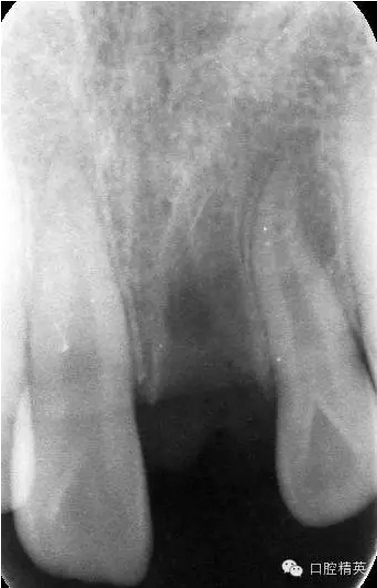

x線檢查:21牙槽窩空虛,窩內(nèi)未見(jiàn)其他遺留物。

圖4.脫落的21離體牙,根面污染嚴(yán)重